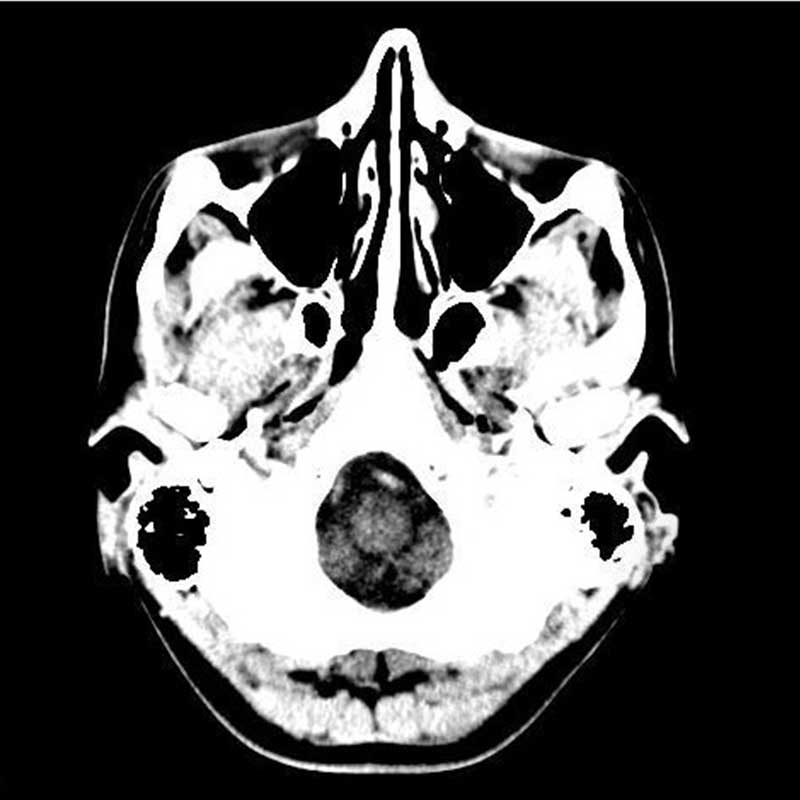

The Curious Case of Severe Traumatic Brain Injury

by Dr. John Leggins

The Curious Case of Severe Traumatic Brain Injury

by Dr. John Leggins